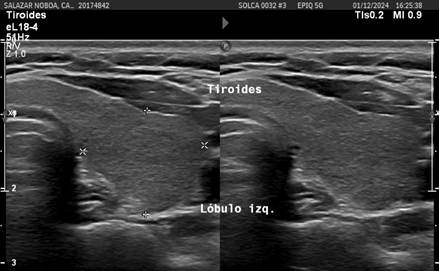

A PET-CT scan in December 2023 revealed persistent hypermetabolic lymphadenopathy in the left lateral cervical region (SUVmax 2.4), as well as increased metabolism in the right thyroid lobe. A cervical ultrasound in December 2024 identified a 0.69 x 0.72 cm hypoechoic solid thyroid nodule, classified as TIRADS 4A (Figure 3). The fine-needle aspiration biopsy (FNAB) was reported as Bethesda IV, and management was decided upon with close monitoring.

Figure 3

Cervical ultrasound: Thyroid nodule classified as TIRADS 4A.

2661-6653-onco-35-03-26-gf3.jpg

Source: SOLCA Intranet - Guayaquil.